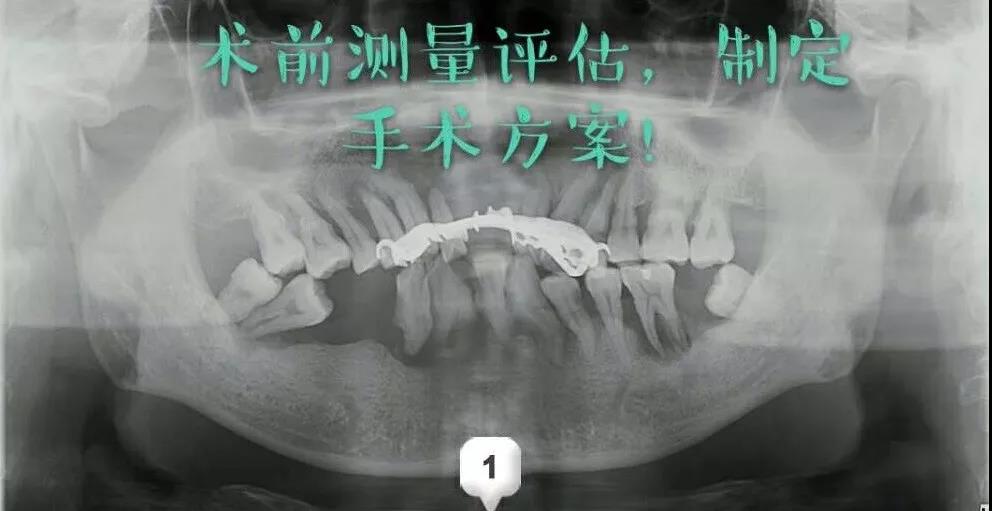

ЁЁЁЁЁОвЊЮХЁПФъНі48ЫъЕФЫћбЯжибРжмВЁбРГнМИКѕЕєЙтЃЌдкЪЅНрПкЧЛжиЛёПкИЃ!

ЁЁЁЁдчЩЯЦ№РДЫЂбРЪБЃЌбРЫЂЩЯгабЊ;ееееОЕзгЃЌЗЂЯжбРіИКьжз;ЧзХѓКУгбвВ“добя”ФуЕФПкЦјДѓ……ЕБГіЯжвдЩЯжЂзДЪБ,бРжмВЁвбО“ПДЩЯСЫ”Фу,ФЧУДЃЌЧыБ№АббРжмЕБЖљЯЗ,вЛЭЯдйЭЯФ№ДѓДэ!

ЁЁЁЁМђЕЅЕФЫЕЃЌбРжмВЁЪЧЪЙбРГн“ЕиЛљ”СїЪЇЕФМВВЁЁЃЪЧГЩФъШЫбРГнШБЪЇЕФжївЊдвђЁЃвВЪЧЮЃКІШЫРрбРГнКЭШЋЩэНЁПЕЕФжївЊПкЧЛМВВЁЁЃ

ЁЁЁЁГЃМћЕФбРжмВЁАќРЈЃКбРіИбзКЭбРжмбз

ЁЁЁЁбРіИбзНзЖЮЃКбРіИКьжзГібЊЃЌбРГнжмЮЇгабРЪЏЁЃ

ЁЁЁЁдчЦкбРжмбзЃКГ§бРіИбзжЂЭтЃЌбРжмДќаЮГЩЃЌбРВлЙЧЧсЖШЮќЪеЁЃ

ЁЁЁЁжаЦкбРжмбзЃКбРжмДќНјвЛВНМгЩюЃЌбРГнЫЩЖЏЁЂвЦЮЛЁЃ

ЁЁЁЁЭэЦкбРжмбзЃКбРВлЙЧМИКѕЭъШЋБЛЦЦЛЕЃЌбРГнЫЩЖЏЁЂЭбТфЁЃ

ЁЁЁЁЪЅНрПкЧЛгРаЫТЗдКжжжВПЦЕФВмН№ЗхжїШЮЮЊМжЯШЩњжЦЖЈСЫМДАЮМДжжЕФжжжВЗНАИЃЌдкАЮГ§ЛМбРЕФЭЌЪБжВШыжжжВЬхЃЌВЩгУALL-ON-6ШЋПкжжжВММЪѕХфКЯ3DДђгЁММЪѕКЭЪ§зжЛЏжжбРЕМАхЃЌШЋПкжжжВМгЩЯМДПЬИКжиЃЌЪЧЗЧГЃгааЇЕФбРСажиНЈЗНАИЁЃ